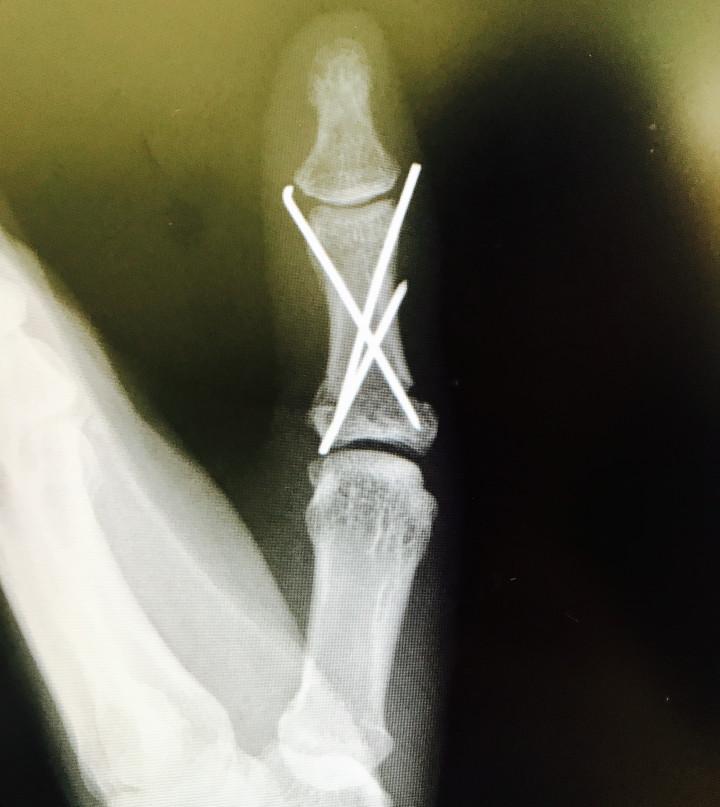

8月くらいに遊具で遊んでいました。

約4メートルから落下し

親指を粉砕骨折しました。

でも、傷は一切ありませんでした。

全治6ヶ月の診断でしたが、

2ヶ月という驚異の回復力を発揮して完治。

冬場なので、痛みがありますが、

もう、生活に支障はありません。